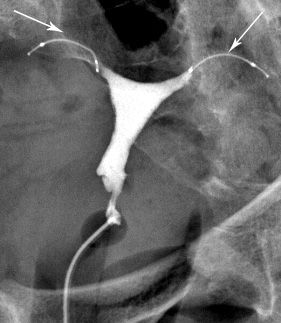

L’examen a pour but d’étudier la cavité utérine et la perméabilité des trompes.

Elle est réalisée par voie endovaginale après introduction d’un spéculum (comme lors d’un examen gynécologique).

Le produit opaque injecté rend visible sur les radiographies la cavité utérine et les trompes. Cet injection provoque une gène comparable à celle ressentie lors de règles douloureuses.

Les radiographies sont effectuées avant, pendant et après l’opacification.La préparation